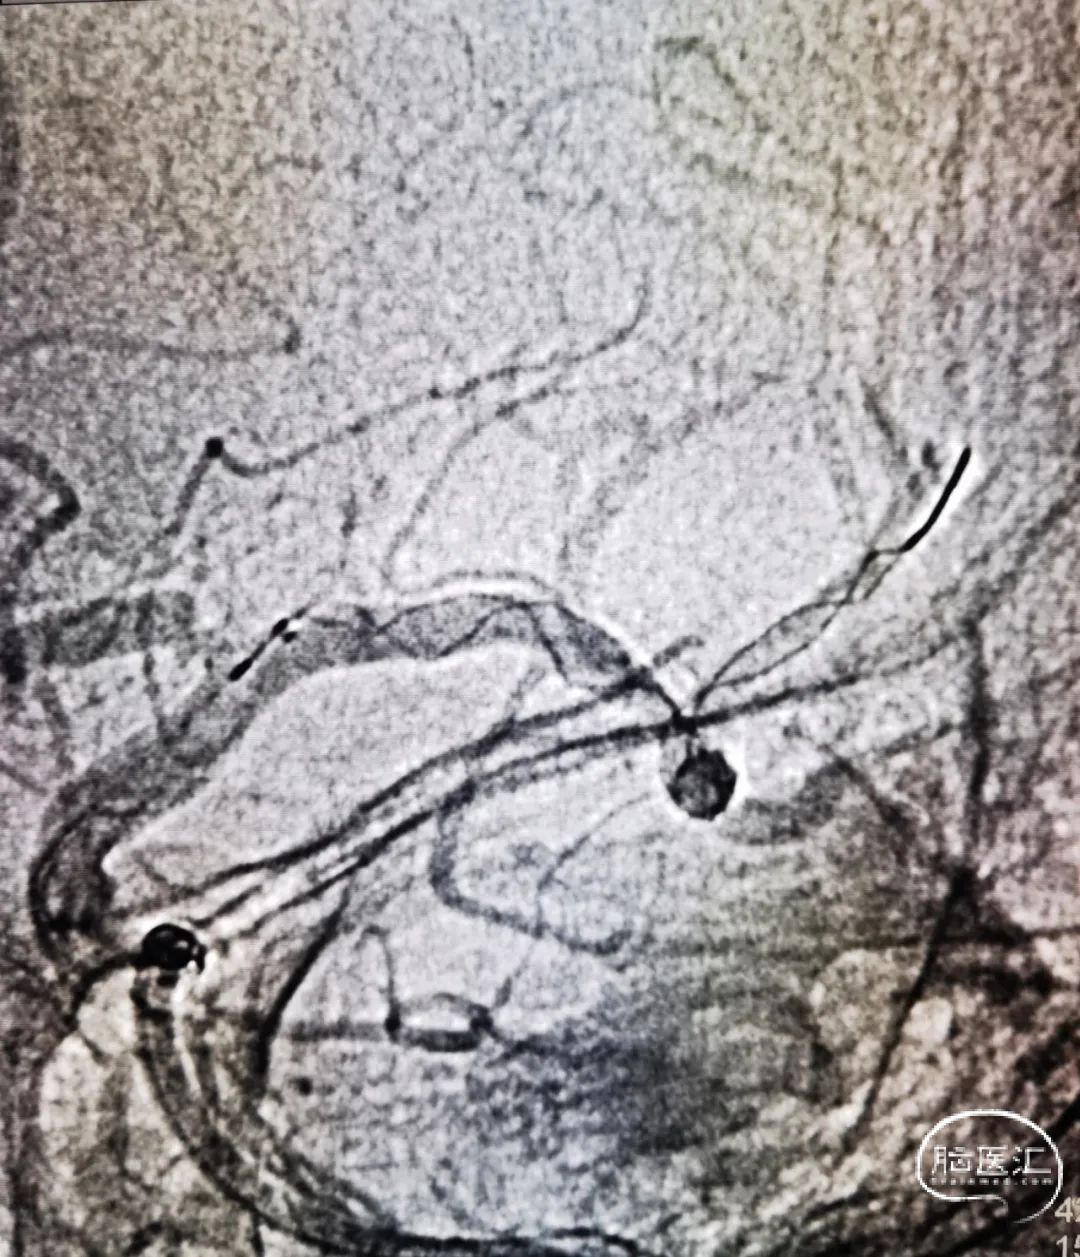

术中造影确认脑血流完全恢复,mTICI 3级,术后24小时复查头颅CT左顶叶少量渗出。

术后7天后患者NIHSS评分改善。CT提示渗出基本吸收,有部分缺血表现。

神志嗜睡,言语含糊,查体欠合作,双侧瞳孔等圆等大,直径约3.0mm,双瞳直接及间接光反射灵敏,右侧鼻唇沟变浅,伸舌居中,颈软,四肢腱反射正常,四肢肌力适中,左侧肢体肌力V级,右侧肢体肌力III级,双下肢病理反射阴性。出院前mRS 4分,NIHSS:8分。已转当地医院进一步康复治疗,仍在随访中。